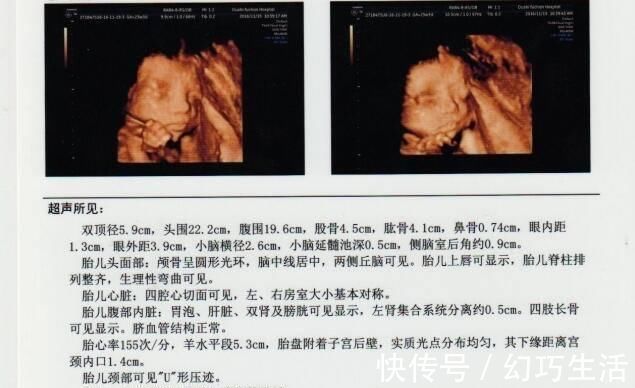

其实对孕妈来说,检查报告最不明确的应该是各个数据的意义,比如图示的双顶径5.9cm,这个双顶径是什么?5.9cm标准吗?对胎儿有哪些影响呢?所以说,只要明确了几个重要数据的意义,那检查报告对孕妈来说,看起来就会很容易了。

如图示,羊水平段5.3cm。这个羊水平段,也就是羊水深度,是指B超检查的最大羊水池的垂直深度,正常范围为3-8cm,小于3cm羊水过少,大于8cm羊水过多,过多多少都得重视。

胎心率也是每次B超检查必须的,对胎儿来说非常重要,胎心率正常值为120-160次/分钟,如果低于120次/分钟,或者高于160次/分钟,都代表胎儿宫内异常,可能有缺氧危险。